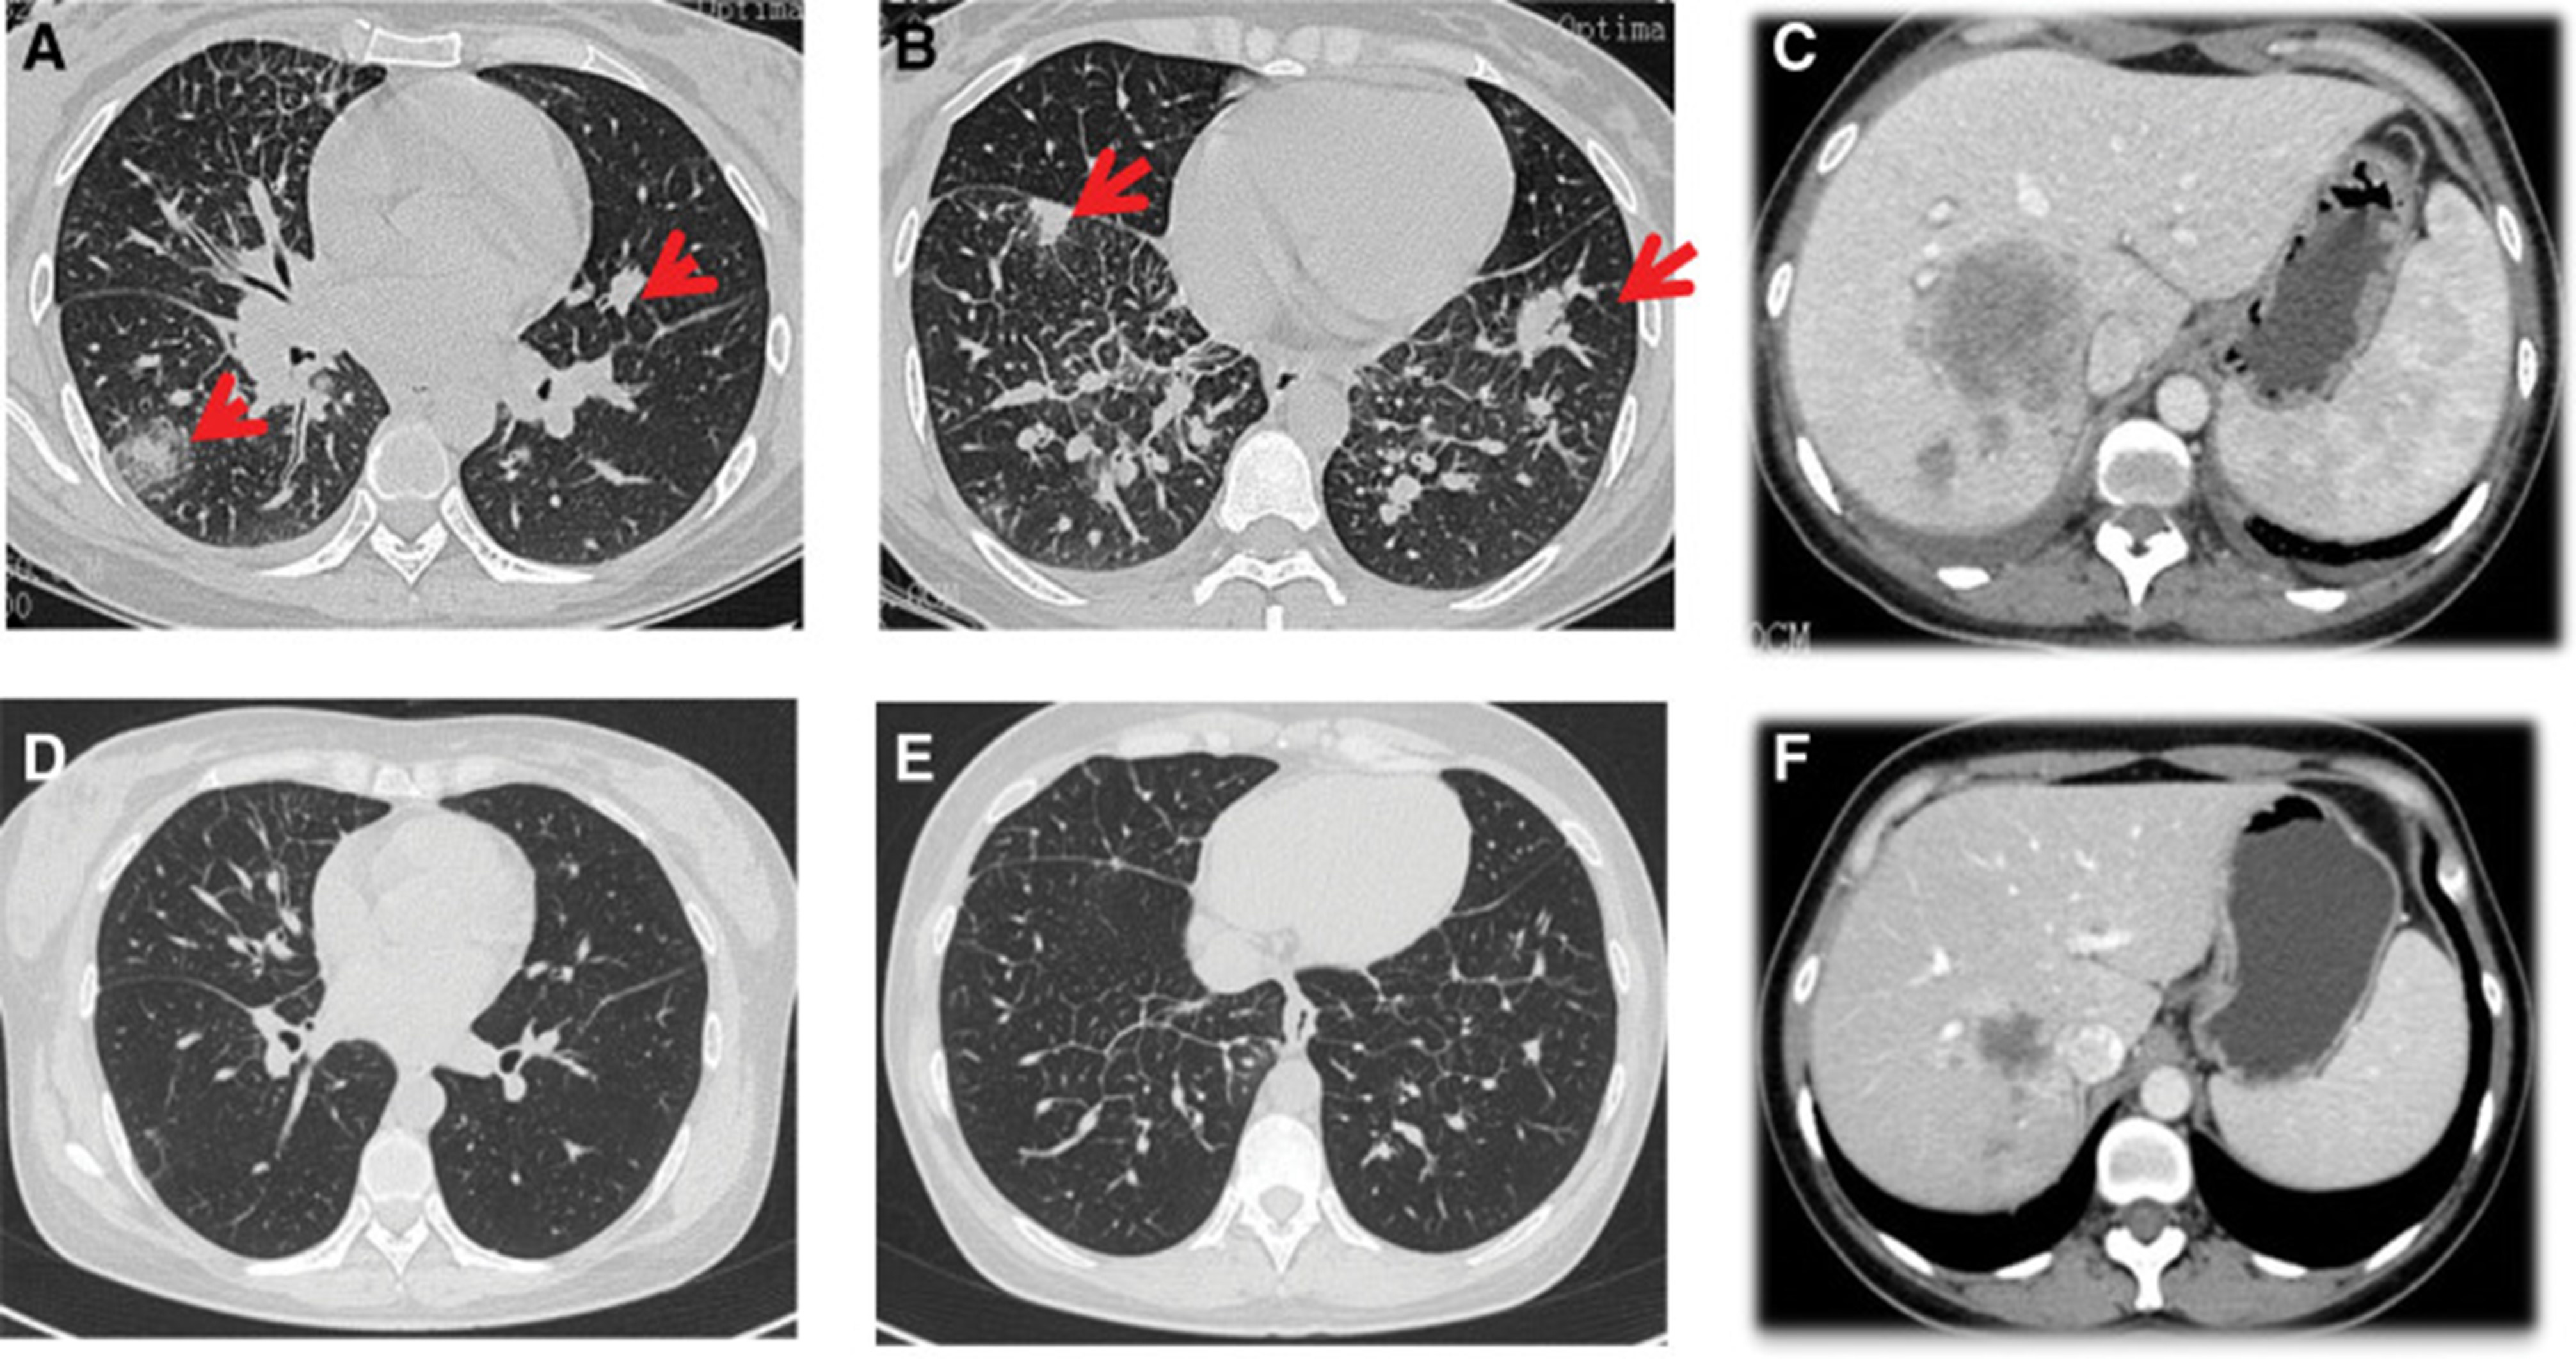

2020年4月,患者胸部CT示“双肺多发结节,纵隔及肺门多发肿大淋巴结;附着于肝右叶,略呈低密度肿块影”(图 1)。(图4A,4A、B)和腹部CT显示“肝脏多发肿块”(图1)。(图 4C)。骨扫描显示“身体多个部位的骨代谢异常增强”。2020年4月19日,对“右肝肿块和右锁骨上肿块”进行活检,病理指征(右肝肿块抽吸、右锁骨上肿块抽吸)为低分化腺癌。结合免疫组化结果,首先考虑的是肺腺癌转移。贼终诊断为“IV期肺腺癌伴多发肝和骨转移”。基因检测显示“EML 4-ALK 融合,PD-L1 肿瘤阳性细胞数TPS 80%”(图 2)。(图1和和2)。

和 2020 年 6 月 (D-F).jpg)

图 4:2020 年 4 月 (A-C) 和 2020 年 6 月 (D-F) 的 CT 扫描。CT = 计算机断层扫描。

2020年5月1日,患者开始口服艾乐替尼靶向药物进行治疗,2020年6月25日复查,确定治疗效果为PR(部分有效)(根据RECIST1.1)显示肺病灶和肝转移灶明显减少(图1)。(图 3D-F)。2020 年 8 月 27 日复查确定治疗效果为疾病进展(PD, progressive disease),根据 RECIST1.1显示肝脏病变变大(图 1)(图 4A-D)。进行了第二次肝活检,随后的病理学显示“(肝)低分化癌,结合免疫组织化学分析考虑肺腺癌转移”。组织活检进行了第二轮基因检测,结果显示“BRAFV600E 14.79%,EML 4-ALK fusion 14.47%”(图 1)(图 5)。2020年9月20日,对患者我以为用恩沙替尼联合达拉非尼靶向治疗。治疗开始后,患者出现明显发热、寒战、乏力和厌食。期间患者左侧出现大量胸腔积液,胸腔积液中脱落细胞为“非典型细胞,考虑为腺癌”。随后,该患者接受了 1 次胸腔内铂输注。

和 2020 年 8 月.jpg)

图 5:2020 年 6 月(A 和 B)和 2020 年 8 月(C 和 D)的 CT 扫描。CT = 计算机断层扫描。

1个月后复查显示肺部和肝内病变进展(图1)。(图 6A-C)(根据RECIST1.1),她的抗肿瘤治疗改为“培姆曲塞加卡铂和贝伐单抗”的治疗一个周期。2020年12月至2021年1月,再次改变患者的治疗方案,这次改为“劳拉替尼联合达拉非尼”靶向治疗。使用 PD 联合胸部和腹部 CT 评估疗效(图 1)。(图 6D-F)(根据 RECIST1.1)。患者无法耐受化疗、靶向治疗、IO 治疗或任何其他积极的抗肿瘤治疗。这是因为患者的一般情况较差,包括发烧、腹痛和胆红素水平升高等症状。随后,给予患者静脉营养、镇痛等对症支持治疗。患者于 2021 年 2 月 4 日去世,总生存期(OS)为 10 个月。

和 2022 年 1 月 (D-F) 的 CT 扫描.jpg)

图 6:2020 年 11 月 (A-C) 和 2022 年 1 月 (D-F) 的 CT 扫描。CT = 计算机断层扫描。